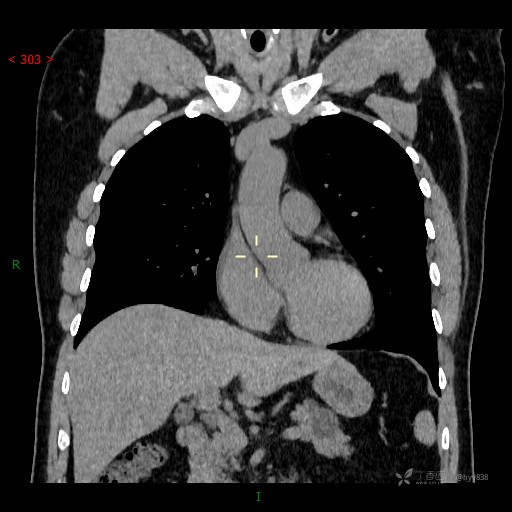

晨读误诊病例。体检发现胰腺占位,病史仅供参考,请讨论---结果公布~

临床诊断:胰腺占位